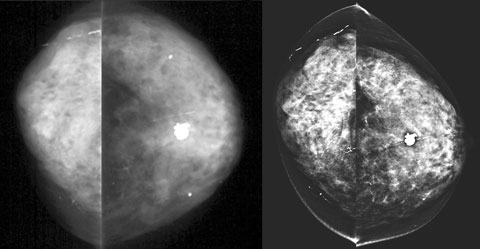

The sensitivity of DM is at least equal to CM for detection of breast cancer.17-21 A recent study of over 49 000 women showed DM to be more diagnostically accurate than CM in women under 50 years of age, women with radiographically dense breasts and pre- or peri-menopausal women.21 Underlying this clinical finding is the proven superior contrast resolution of DM, giving it maximal impact in radiographically dense breast tissue that may mask a dense cancerous mass.22 In our patient cohort, we subjectively found that imaging of dense breasts improved with DM compared with CM (Box 5). With growing debate about whether to invite women aged 40–49 years to screening by BreastScreen, the greater accuracy of DM in dense breasts is particularly pertinent.23